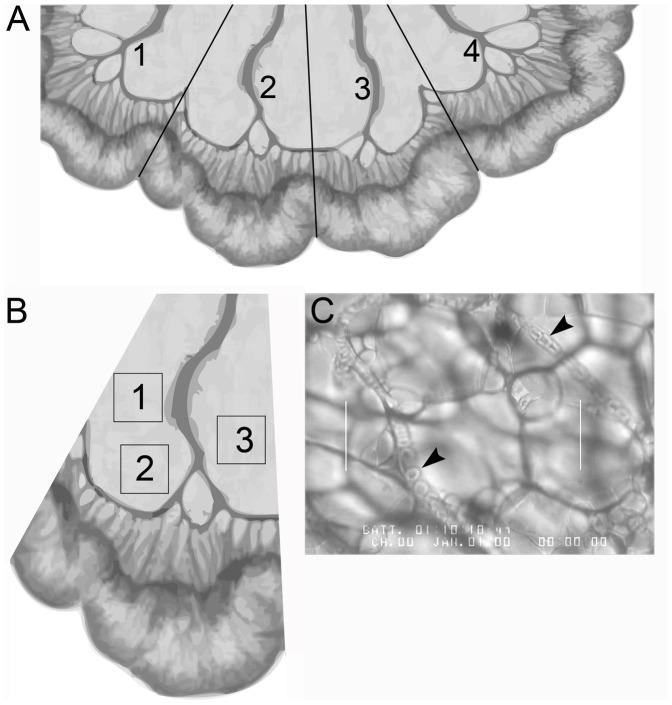

Host allelic variation controls the response to B. anthracis and the disease course of anthrax. Mouse strains with macrophages that are responsive to anthrax lethal toxin (LT) show resistance to infection while mouse strains with LT non-responsive macrophages succumb more readily. B6.CAST.11M mice have a region of chromosome 11 from the CAST/Ei strain (a LT responsive strain) introgressed onto a LT non-responsive C57BL/6J genetic background. Previously, B6.CAST.11M mice were found to exhibit a rapid inflammatory reaction to LT termed the early response phenotype (ERP), and displayed greater resistance to B. anthracis infection compared to C57BL/6J mice. Several ERP features (e.g., bloat, hypothermia, labored breathing, dilated pinnae vessels) suggested vascular involvement. To test this, Evan's blue was used to assess vessel leakage and intravital microscopy was used to monitor microvascular blood flow. Increased vascular leakage was observed in lungs of B6.CAST.11M mice compared to C57BL/6J mice 1 hour after systemic administration of LT. Capillary blood flow was reduced in the small intestine mesentery without concomitant leukocyte emigration following systemic or topical application of LT, the latter suggesting a localized tissue mechanism in this response. Since LT activates the Nlrp1b inflammasome in B6.CAST.11M mice, the roles of inflammasome products, IL-1β and IL-18, were examined. Topical application to the mesentery of IL-1β but not IL-18 revealed pronounced slowing of blood flow in B6.CAST.11M mice that was not present in C57BL/6J mice. A neutralizing anti-IL-1β antibody suppressed the slowing of blood flow induced by LT, indicating a role for IL-1β in the response. Besides allelic differences controlling Nlrp1b inflammasome activation by LT observed previously, evidence presented here suggests that an additional genetic determinant(s) could regulate the vascular response to IL-1β. These results demonstrate that vessel leakage and alterations to blood flow are part of the rapid response in mice resistant to B. anthracis infection.

宿主等位基因变异控制炭疽杆菌的反应和炭疽病的病程。对炭疽致死毒素(LT)有反应的巨噬细胞的小鼠品系对感染表现出抵抗力,而 LT 无反应的巨噬细胞的小鼠品系更容易屈服。B6.CAST.11M 小鼠具有来自 CAST/Ei 品系(LT 有反应的品系)的 11 号染色体区域,被引入 LT 无反应的 C57BL/6J 遗传背景。此前,B6.CAST.11M 小鼠被发现对 LT 表现出快速炎症反应,称为早期反应表型(ERP),并且与 C57BL/6J 小鼠相比,对炭疽杆菌感染表现出更大的抵抗力。一些 ERP 特征(例如,肿胀、体温过低、呼吸困难、耳廓血管扩张)表明血管参与。为了测试这一点,使用 Evan's blue 评估血管渗漏,并使用活体显微镜监测微血管血流。与 C57BL/6J 小鼠相比,B6.CAST.11M 小鼠在全身给予 LT 后 1 小时,其肺部的血管渗漏增加。在全身或局部应用 LT 后,小肠肠系膜中的毛细血管血流减少,但没有白细胞迁移,后者表明该反应存在局部组织机制。由于 LT 在 B6.CAST.11M 小鼠中激活 Nlrp1b 炎性体,因此检查了炎性体产物 IL-1β 和 IL-18 的作用。局部应用于肠系膜的 IL-1β 但不是 IL-18,在 B6.CAST.11M 小鼠中明显减缓血流,而在 C57BL/6J 小鼠中则不存在。中和抗 IL-1β 抗体抑制了 LT 诱导的血流减缓,表明 IL-1β 在该反应中的作用。除了之前观察到的控制 LT 激活 Nlrp1b 炎性体的等位基因差异外,这里提出的证据表明,其他遗传决定因素可能调节对 IL-1β 的血管反应。这些结果表明,血管渗漏和血流改变是对炭疽杆菌感染具有抵抗力的小鼠快速反应的一部分。